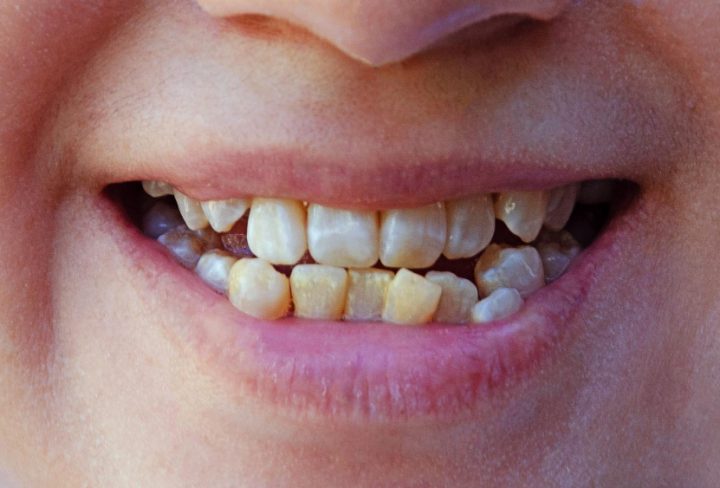

Dental fluorosis is a change in the appearance of tooth enamel. It happens when children get too much fluoride while their teeth are forming. Usually, this condition shows up as white spots or streaks on the teeth. In some cases, the spots may be brown or pitted. Although dental fluorosis does not harm health, it can affect how teeth look. Many parents want to know the causes of dental fluorosis and how to prevent it. Understanding this condition can help you keep your child’s smile bright and healthy.

When children get too much fluoride, it affects the way their teeth form. Normally, fluoride helps make teeth strong and prevents cavities. However, too much fluoride can cause the enamel to form unevenly. As a result, teeth may have white lines, spots, or even brown stains. In rare cases, the surface of the teeth may become rough or pitted. Still, dental fluorosis does not cause pain or tooth decay. But, it can make people feel self-conscious about their smile. For this reason, it is important to watch how much fluoride children get.